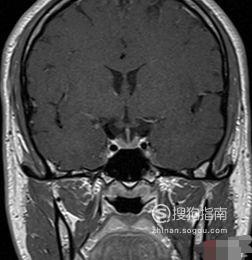

汤氏位:

摄影目的:诊断枕骨鳞部病变(骨折、骨髓炎、枕疝等)、枕大孔病变及颞骨岩部病变(听神经瘤、胆脂瘤等)

摄影体位:患者仰卧于摄影台上,两臂放于身旁;然后让患者头正中矢状面垂直床面并与暗盒中线重合;患者下颌内收,使听眦线与床面垂直;胶片上缘与头顶平齐,下缘抵下颌骨;采用滤线器或滤线栅摄影,摄影距离为10O厘米

中心线:向足侧倾斜30°,经眉间上方约10厘米处射入,从枕外隆凸下方射出。